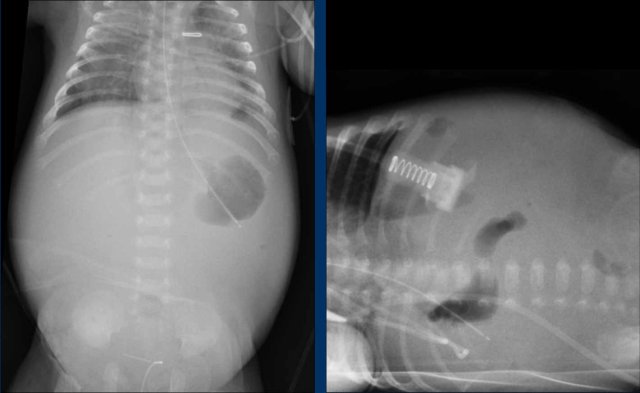

Images

There is a nearly gasless or ‘white abdomen’ in a previously normal gas distribution.

There is only a small amount of free air present under the diaphragm.

For small amounts of free air ultrasound is more sensitive.

Ultrasound may also show focal and dirty ascites which is very suggestive of a perforation.